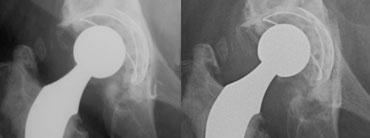

LEFT: Hybrid THA with cemented femoral stem and noncemented acetabular cup.RIGHT: Bone ingrowth arthroplasty. Density lateral to femoral stem in Gruens zone I is a bone graft.

Thay khớp háng toàn phần lai là sự kết hợp giữa cố định có xi măng và không xi măng.

Do các thành phần ổ cối có xi măng có xu hướng bị lỏng theo thời gian, đôi khi người ta sử dụng kết hợp thành phần ổ cối không xi măng với thành phần xương đùi có xi măng.

Nhìn chung, có xu hướng ưu tiên sử dụng thay khớp háng toàn phần không xi măng, vì cho kết quả lâu dài tốt hơn.

Bên trái chúng ta thấy một khớp háng nhân tạo toàn phần (THA) lai ghép với cốc ổ cối tích hợp xương và thân xương đùi gắn xi măng, và bên cạnh đó là một khớp háng nhân tạo toàn phần không xi măng tích hợp xương.